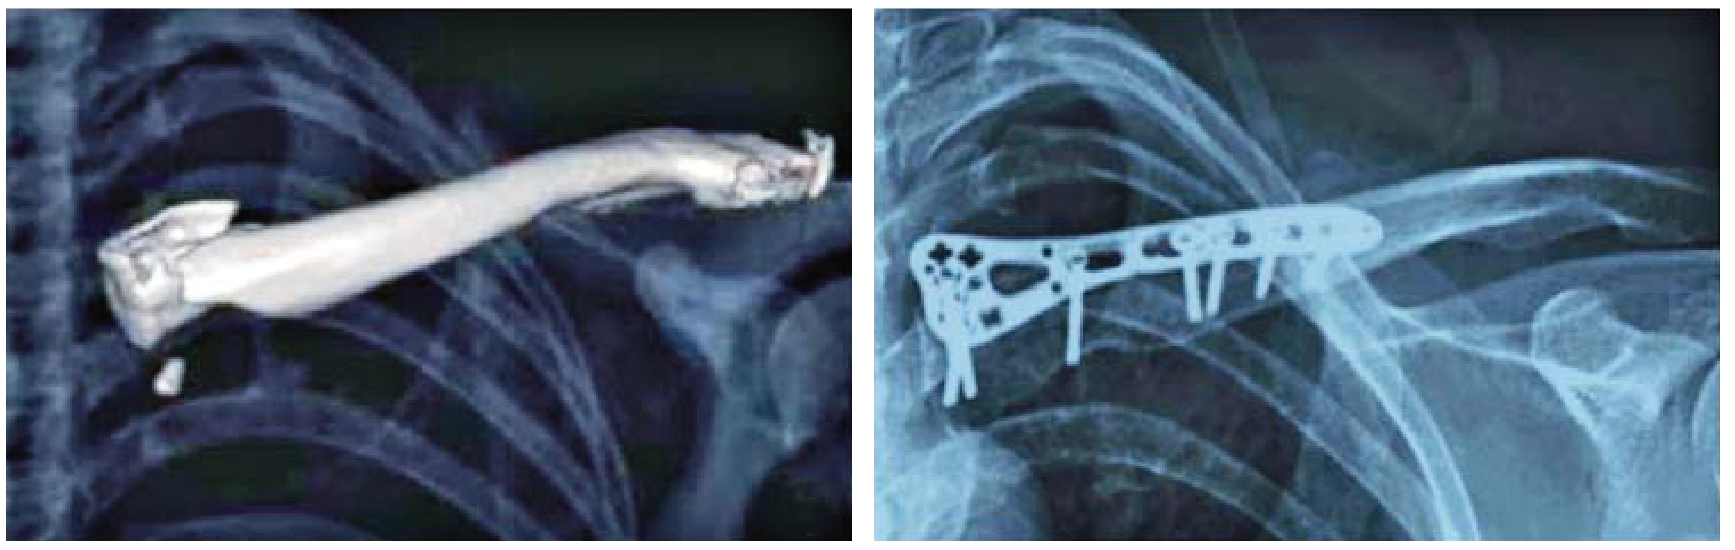

锁骨近端骨折手术治疗方法繁多,尚无统一标准。按内固定装置的不同,手术方式包括:单纯克氏针内固定术、克氏针张力带内固定术、螺钉内固定术、钢板内固定术等。单纯克氏针固定及克氏针钢丝张力带技术具有操作简单、术中软组织损伤小、对骨折周围的血运影响小等优点,但克氏针牢固性较差,无法满足患者早期功能训练的需要,且克氏针易松动、退针、游走及断裂并发症高,临床已很少应用。近年来多数学者主张采用锁定钢板治疗锁骨近端骨折,但目前尚无专用于锁骨近端骨折的钢板问世。部分学者采用桡骨远端锁定钢板、同侧锁骨远端锁定钢板倒置、T型钢板取得了良好的疗效,但样本量仍较小,需进一步的临床实践证实(图1—6、1—7)。解剖学研究发现,胸锁关节在各个方向均具有一定的活动度,其中上下30°~35°,前后35°,并可沿纵轴旋转45°~50°,因此对于胸锁关节应采取弹性固定。如果因为近端骨折块较小而采取跨胸锁关节固定,那么势必引起胸锁关节处钢板应力的增加,造成螺钉松动甚至钢板断裂,因此对于跨胸锁关节固定应谨慎。

图1—6 桡骨远端锁定钢板治疗锁骨近端骨折

图1—7 同侧锁骨远端锁定钢板反置治疗锁骨近端骨折